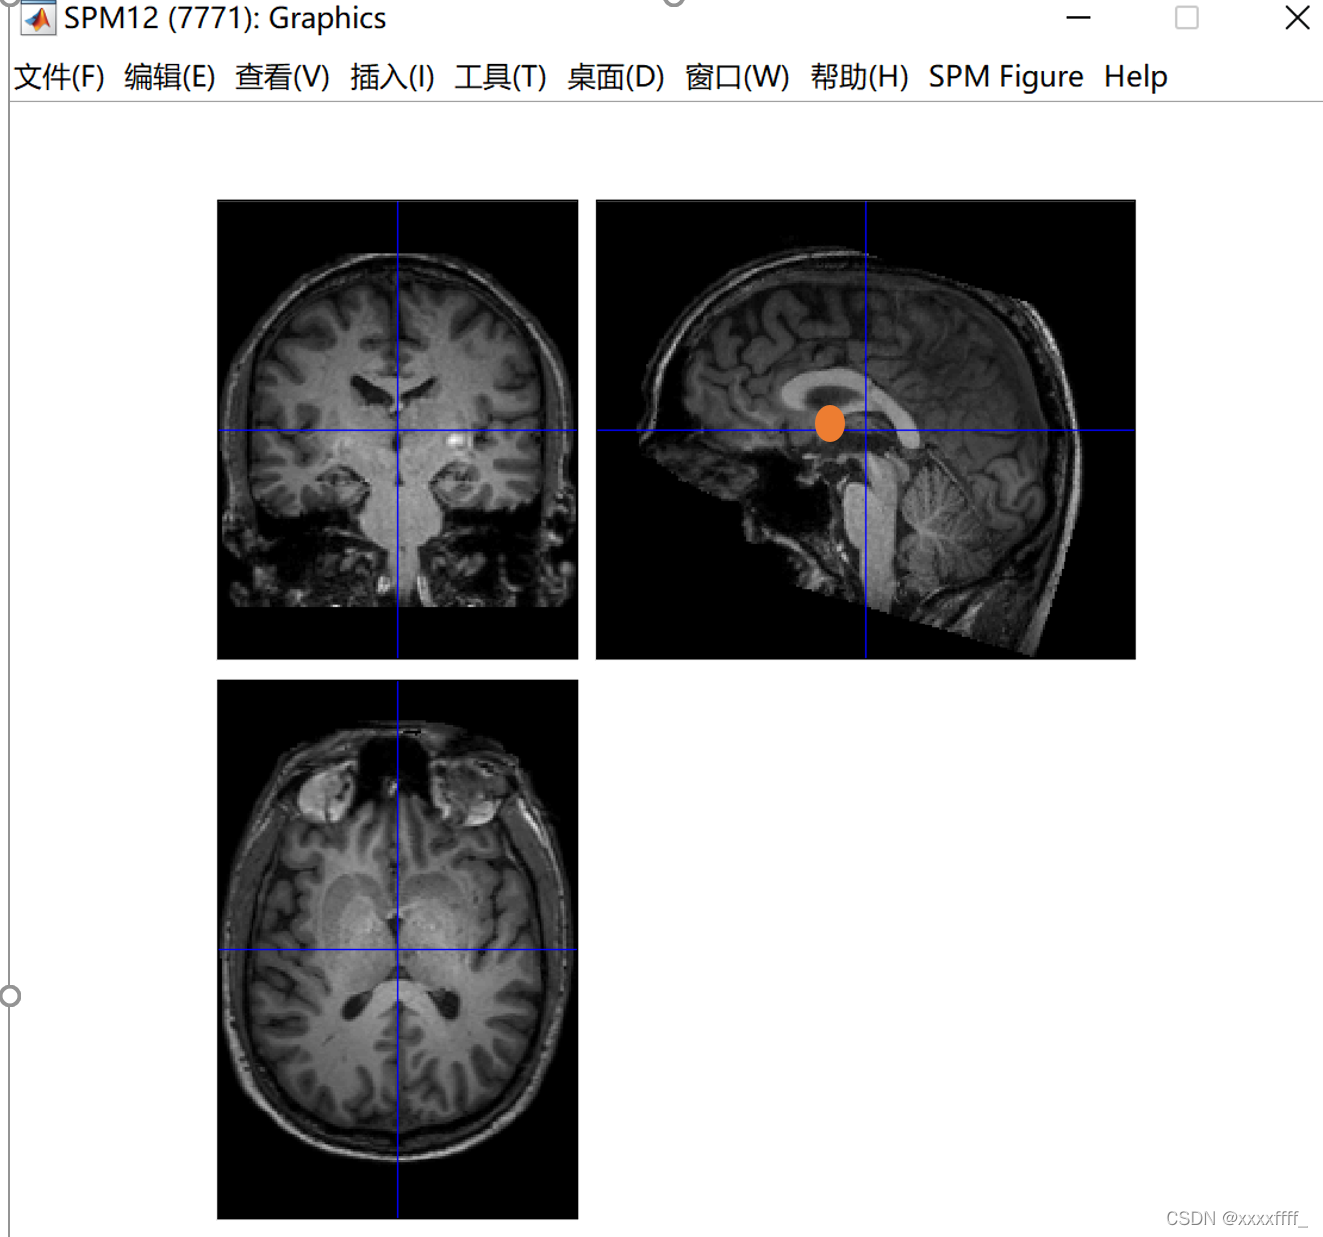

一个这样的页面,我们可以看到一个蓝色的十字线,这个线的交叉点就是我们要调整的地方,手动将交叉点放在大概下图这个位置(就是前联合的位置),前联合的位置怎么确定可以去查一下,网上有很多教程。我的理解就是大概在下图这个红色的圆里。点一下set origin之后就会出现坐标位置。然后一定要点击一下Reorient,才算是调整成功了。